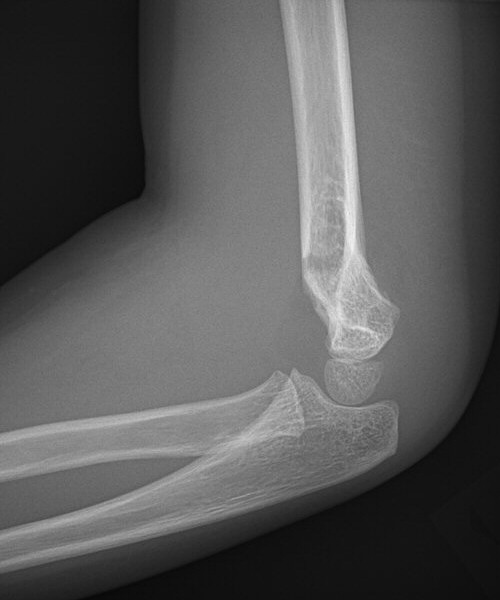

Suprakondylär humerusfraktur, Gartland 2, opererades med stiftning